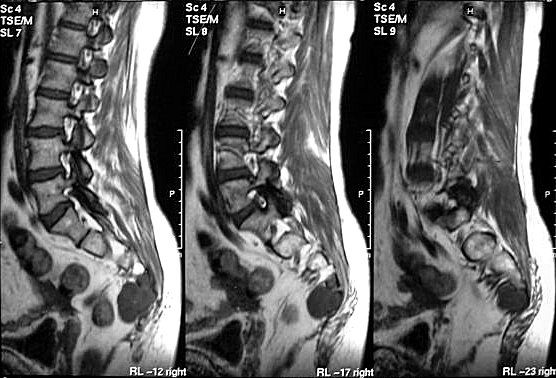

Сакральная хордома. Д-р Марсело Сенна Ксавье де Лима, Paul Roland Kaleff, и Антонио Рожерио del'Arco Roth Аугусто Варгас. Рецидив. Часть крестца была удалена ранее. Пнд, 27/11/2017 - 21:03 #1 Катенёв Валенти... Не на сайте Был на сайте: 7 лет 4 месяцев назад Зарегистрирован: 22.03.2008 - 22:15 Публикации: 54876 Внутричерепная хордома. http://pubs.rsna.org/doi/full/10.1148/rg.234025176 Пнд, 09/07/2018 - 20:44 #2 Катенёв Валенти... Не на сайте Был на сайте: 7 лет 4 месяцев назад Зарегистрирован: 22.03.2008 - 22:15 Публикации: 54876 Продолжение. Приложения: